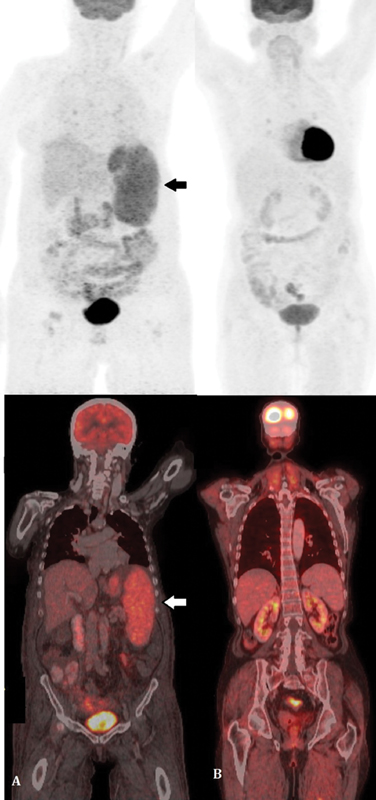

Computed tomography (CT) scan reported hepatosplenomegaly (liver, 17.3?cm and spleen, 16.8?cm), splenic infarct, dilated portal vein with splenic collaterals, ascites, and bilateral pleural effusion. Positron emission tomography?computed tomography (PET-CT) scan highlighted diffuse metabolic uptake in the enlarged spleen, avid bilateral pleural effusion, and diffuse subcutaneous edema ([Fig. 1A]). Bone marrow examination showed cellular aspirate with trilineage hematopoiesis without any abnormal cells. There was an increase in monohistiocytic cells with few showing hemophagocytosis. CD68 done on bone marrow biopsy highlighted the mono-histiocytic cells. Since there was no clinical suspicion of lymphoma and the marrow was reactive on morphology without any suspicious or abnormal cells, flow cytometry was not done.

|?Fig. 1? Positron emission tomography?computed tomography (PET-CT) scan of the patient. (A) The pre therapy scan shows diffuse metabolic uptake in the enlarged spleen, (B) posttherapy scan revealed no metabolically active disease focus, thus indicating complete response. Arrow depicts ?large atypical lymphoid cells?.|

The presence of left-sided portal hypertension, coagulopathy, and hypoalbuminemia raised a clinical suspicion of chronic liver disease with high LDH levels and hence liver biopsy was planned. The percutaneous liver biopsy was contraindicated due to pancytopenia and hence transjugular biopsy was performed. Hepatic vein-portal-vein pressure gradient (HVPG) measured during the procedure was within normal limits. Although lymphoma was not suspected clinically at the time of biopsy but surprisingly, the transjugular liver biopsy displayed few large, atypical lymphoid cells within the sinusoids. They exhibited pleomorphic nuclei along with mitotic figures and apoptotic bodies ([Fig. 2A] and [B]). The overall hepatic architecture was preserved with background macrovesicular and microvesicular steatosis and nuclear glycogenation. No bridging fibrosis or cirrhosis was seen. Immunohistochemistry found the large sinusoidal lymphoid cells to be positive for CD20, bcl6 (weak), bcl2 and MUM-1 ([Fig. 2C?E]), while they were negative for CD30, TdT, CD138 and Cyclin-D1. The c-myc stained 40% of the neoplastic B-cell population while Ki-67 proliferation index was around 70% in these cells. A diagnosis of IVLBCL without cirrhosis was rendered. The patient was treated with six cycles of R-miniCHOP which comprised rituximab, 375?mg/m2; cyclophosphamide, 400?mg/m2; adriamycin, 25?mg/m2; vincristine, 1?mg/m2; and prednisolone, 30?mg/m2?daily once for 5 days. She responded with increase in blood counts and albumin with subsequent decrease in pedal edema. At 6-month follow-up, the patient was doing well with normal blood counts and minimal edema. On repeat PET-CT scan, no metabolically active disease focus was detected indicating complete response ([Fig. 1B]).